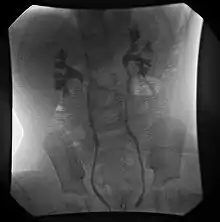

- تصوير المثانة.

- تصوير المثانة، و الإحليل الإفراغي بالكشف الفلوري.

- موجات فوق صوتية على البطن.

- تصوير ومضي (DMSA).

قد تشير الموجات الفوق صوتية على البطن إلى وجود جزر مثاني حالبي، وذلك إذا وُجد اتساع في الحالب. ولكن، في معظم حالات الجزر المثاني الحالبي، قليلة الدرجة، والمعتدلة، وحتى بالغة الخطورة، قد يكون التَخْطيطٌ التَصْوَاتِيِّ طبيعي تماما؛ ولذلك فإنها لا توفر فائدة كافية كاختبار تشخيصي وحيد لتقييم الأطفال المشتبه في وجود جزر مثاني حالبي عندهم، كالذين يعانون من موه الكلية قبل الولادة، وعدوى الجهاز البولي.[3] يعتبر تصوير المثانة، و الإحليل الإفراغي بالكشف الفلوري هو الطريقة المفضلة للترتيب، وإجراء التشخيص المبدأي. ويجب أن يتم ربط مؤشر عالي من الشك بالحالات التي تُعرض بعدوى الجهاز البولي، ويجب أن يتم استبعاد الأسباب التشريحية، وينبغي إجراء تصوير المثانة، والإحليل الإفراغى بالكشف الفلوري، والموجات الفوق صوتية على البطن على هذه الحالات. يستخدم التصوبر الومضي (DMSA ) لتقييم ضرر المتني، والذي يتم رؤيته كندبة قشرية. بعد أول إصابة بعدوى الجهاز البولي الحموية، يكون الدور التشخيصي للتصوير الومضي هو اكتشاف الضرر قبل استخدام تصوير المثانة، والإحليل الإفراغي بالكشف الفلوري، والذي يتم استبعاده في الأطفال الذين ليس لديهم ندوب قشرية، أو اتساع في مجرى البول.[4][5] يعتبر التشخيص المبكر في الأطفال أمر بالغ الأهمية، كما أظهرت الدراسات أن الأطفال الذين يعانون من الجذر المثاني البولي، الذين يقدمون مع عدوى الجهاز البولي، والتهاب الحويضة، والكلية الحاد المرتبطة بهم أكثر عرضة للإصابة بتندب القشرية الكلوي الدائم من أولئك الأطفال دون جذر مثاني بولي، مع نسبة خلاف 2.8.[6] وبالتالي فإن الجزر المثاني البولى لا يزيد فقط من معدل الإصابة بعدوى الجهاز البولي، ولكن أيضا يزيد من خطر الأضرار التي تلحق بالهياكل البولية العليا، والمرحلة النهائية للمرض الكلوي (بالانجليزية: End Stage Renal Disease ).[7]